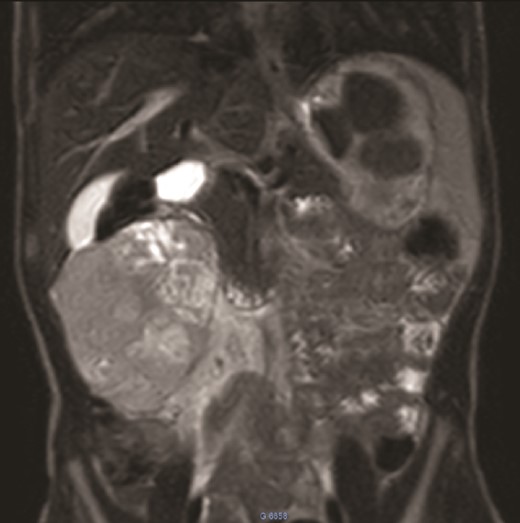

We present the case of an 8-year-old boy with no significant medical history and no prenatal diagnosis of congenital renal malformation. During a physical examination following a minor abdominal injury sustained while playing, a right flank abdominal mass was discovered. Clinically, the patient’s general condition was stable. The mass was non-tender, firm, and fixed to deep planes while mobile over superficial planes. There was no evidence of varicocele. Abdominal ultrasonography and computed tomography (CT) revealed a well-circumscribed, well-encapsulated solid mass measuring 9 × 6 cm, with areas of necrosis. The mass was located in the right kidney, in contact with the cephalic portion of the pancreas and closely abutting the inferior vena cava, which was displaced to the left. The right kidney was not visualized, and no secondary lesions were detected (Fig. 1). Magnetic resonance imaging (MRI) was performed to further characterize the tumor’s origin. However, it confirmed only the presence of the tumor and the absence of normal renal parenchyma, providing no additional information regarding the origin of the upper right abdominal quadrant mass (Fig. 2). Given the unclear origin of the tumor, a CT-guided biopsy was performed. Pathological analysis of the biopsy revealed nephroblastoma without signs of anaplasia. The patient was subsequently treated with neoadjuvant chemotherapy, consisting of vincristine and actinomycin D for 4 weeks, following the SIOP 2001 protocol, and was scheduled for nephrectomy. Post-chemotherapy CT evaluation demonstrated a 75% reduction in the size of the right kidney mass (Fig. 3). The patient underwent an open nephrectomy. Intraoperatively, an atretic ureter was identified, with no visible normal renal parenchyma. An extended right nephrectomy was performed (Fig. 4a and b).

MRI: A solid mass in the upper right of the abdomen without visualization of normal right kidney parenchyma.